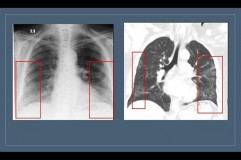

Həkim: "Hazırda “buzlu şüşə” koronavirus pnevmoniyasının əsas radiodiaqnostik əlaməti hesab edilir"